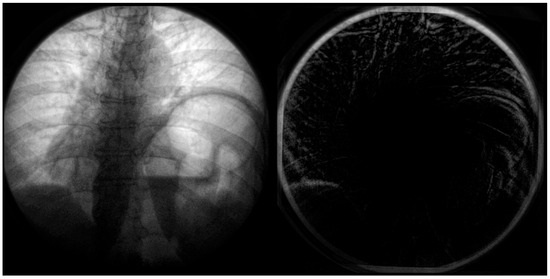

In the below Figure 6, the distortion is most significant radially from the center. This distortion appears primarily on anatomical features such as the ribcage, sternum, and diaphragm (Figure 7). This could significantly impact quantitative assessment if these features were used as landmarks. A side-by-side comparison can be used at the point of the diaphragm to visualize the difference between the calibrated and non-calibrated imagery.

Figure 6. Imagery captured from a fluoroscopic sniff test at peak expiration from a case study of chronic left hemidiaphragm elevation [19]. A frame from the video fluoroscopy was captured pre-application of calibration (left). The geometric distortion coefficient and resulting calibration was applied to the imagery and differenced (right). Note the significant difference in the top of the diaphragm in the left of the image (right) between calibrated and non-calibrated imagery.

Figure 7. Fluoroscopic spot image of the right hemidiaphragm from a fluoroscopic sniff test at peak expiration from a case study of chronic left hemidiaphragm elevation [19]. Calibrated imagery (right) and non-calibrated imagery (left) are compared. The primary shadow along the centerline represents the diaphragm’s surface. The difference in geometric position between calibrated and non-calibrated imagery can be noted.